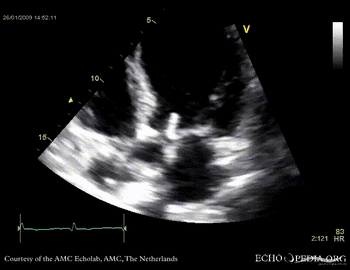

Aortic valve endocarditis with vegetation

Case description: This patient had endocarditis with an aortic valve vegetation

PLAX aortic valve vegetation A3CH aortic valve vegetation